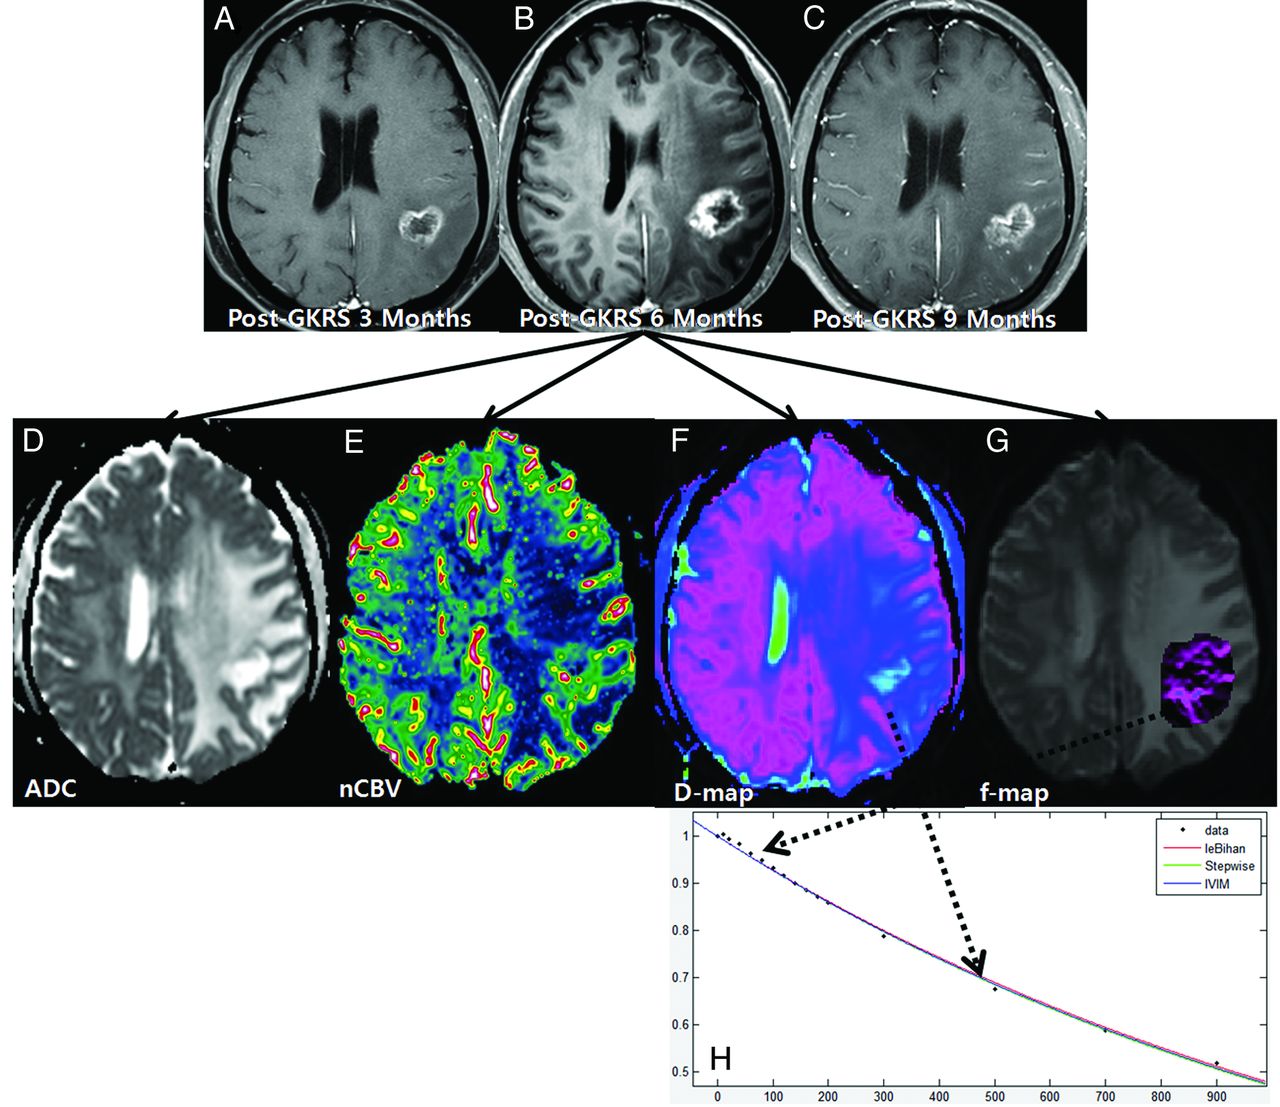

A 61-year-old woman with treatment effect following GKRS. Axial contrast-enhanced T1-weighted images, obtained 3 (A) and 6 months (B) after GKRS, show a progressively enlarging necrotic contrast-enhancing lesion in the left parietal lobe. C, The necrotic contrast-enhancing lesion is stabilized on a subsequent follow-up image obtained 9 months after GKRS, thus indicating treatment effect. The ADC (D) and nCBV (E) maps show no visual decrease of the ADC and no visual increase of the nCBV in the corresponding area of the contrast-enhancing lesion in B, respectively. The D (F) and f (G) maps show no visual decrease of the D value and no visual increase of the f value in the corresponding area of the contrast-enhancing lesion in B, respectively. H, The signal decay curve, plotted as a function of the diffusion b-values, is monoexponential.

Among the 91 study patients, analysis of all of the patients with recurrent tumor and 9 patients with treatment effect showed that the signal decay curve, plotted as a function of the diffusion b-values, was biexponential and ranged from 0 to 900 s/mm2. The recurrent tumor group showed more rapid signal decay than the treatment effect group in the range of lower b-values (b < 200 s/mm2) (Fig 3). In the remaining 43 patients with treatment effect, the signal decay curve was similar to the monoexponential pattern (Fig 2). The f, nCBV, D, and ADC maps of representative cases of recurrent tumor and treatment effect are shown in Figs 2 and 3.